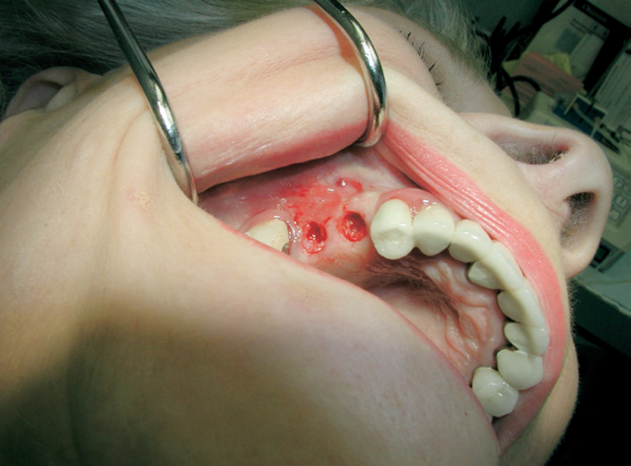

Při ztrátě molárů a premolárů v horní čelisti a jejich náhradě implantáty se často setkáváme s nedostatečnou vertikální nabídkou kosti pod čelistní dutinou, často doprovázenou i nedostatečnou horizontální nabídkou a sníženou kvalitou kosti

(v oblasti 2. premoláru v 50%, v oblasti moláru až v 80% případů nedostatečná kostní nabídka)

Od roku 1985 je tento problém řešen augmentační operací nazývanou sinus lift.

Jedná se o vyzvednutí membrány, která čelistní dutinu vystýlá, pod vyzvednutou membránou vznikne kapsa, kam se umístí augmentační materiál, do kterého se zavedou implantáty.

Vhojení implantátů se při této operaci prodlužuje na 6-12 měsíců.